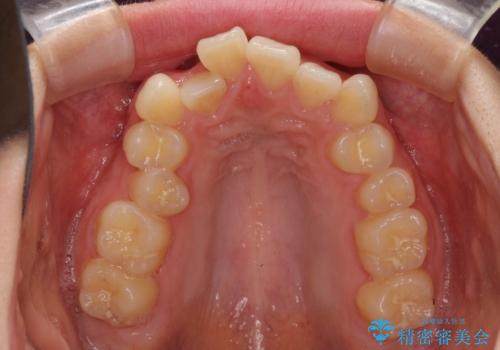

口元の突出感はなく、上顎のみに顕著な叢生が認められました。

上顎の左右第一小臼歯2本を抜歯し、ワイヤー装置にて歯列を整えることとしました。

奥歯の咬み合わせがなかなか定まらず、スペースが閉じるまでに時間がかかりましたが、最終的には正中を合わせることもできました。